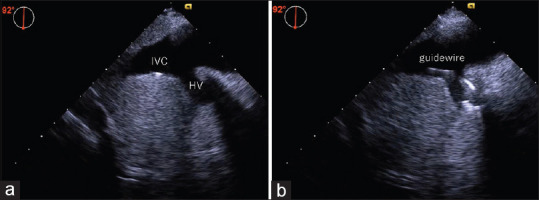

Guidewire Misplacement into the Hepatic Vein During Inferior Vena Cava Cannulation via the Femoral Vein: The Role of Transesophageal Echocardiography.